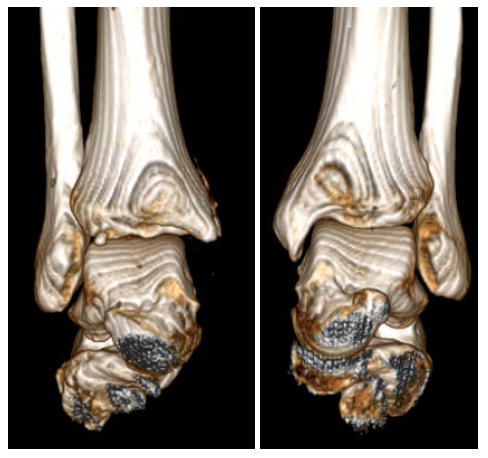

The patient underwent a CT study of the ankle joints with subsequent 3D reconstruction to mo-del the shape of the medial malleolus (Fig. 2, 3).

Fig. 3. Results of 3D reconstruction of both ankle joints